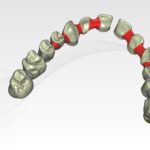

Le projet chirurgical permet d’envisager d’extraire l’ensemble des dents maxillaires et de placer six implants entre 15 et 25 pour la réalisation d’un bridge transvissé de 12 éléments :

Bridge provisoire transvissé réalisé au laboratoire :

Ce bridge a été réalisé en technique d’impression numérique avec création de la fausse gencive par maquillage de surface